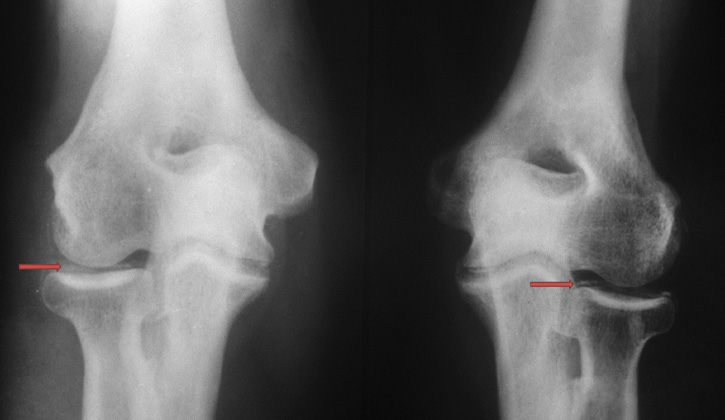

Dấu hiệu X quang: Hình ảnh cơ bản của sụn khớp bị vôi hóa là hiện tượng lắng đọng canxi ở sụn khớp và tổ chức xơ – sụn, tạo thành một lớp mỏng nhìn thấy trên phim như là được “khảm” vào sụn.

- Khớp gối: Gặp 90% các trường hợp, hình cản quang thành một đường song song với lớp xương dưới sụn và nằm ở khoảng giữa, cách xương 3 – 4 cm. Trên phim chụp nghiêng, đường cản quang thấy ở lồi cầu xương đùi tạo hình 2 đường viền. Hình lắng canxi có thể thấy ở sụn chêm (hình tam giác), ở túi dưới cơ tứ đầu đùi của bao hoạt dịch khớp gối.